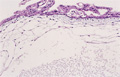

- (13)Hydatidiform mole (complete, partial)

Macroscopic appearance: Almost all of villi shows cystic dilation and most of them larger than 2 mm in their shortest diameter (yellow dotted line).